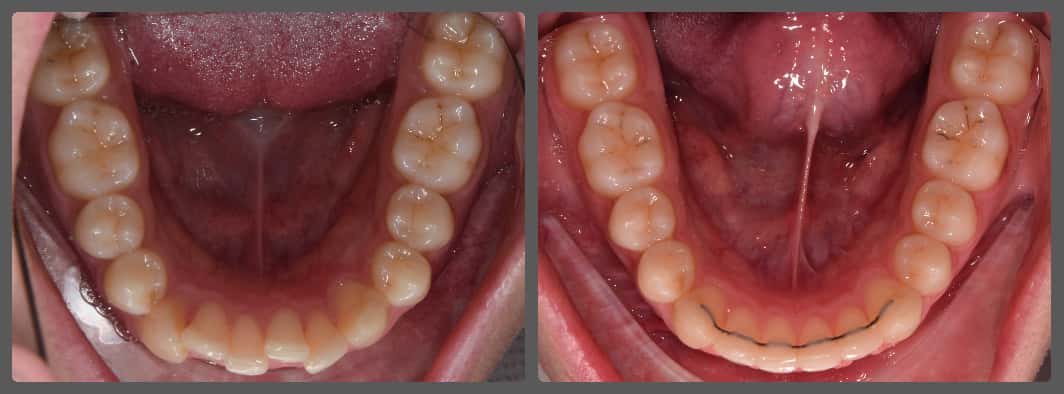

Balázs súlyos alsó torlódása miatt keresett fel magánrendelésemen. A diagnosztikus vizsgálatok során előbbin túl alsó-felső fogívszűkületet, valamint nyitott harapási hajlamot állapítottam meg. Kezelését Pitts21 alsó-felső rögzített fogszabályozó készülékkel kezdtük meg. A nyitott harapási hajlamot a hátsó fogakra helyezett harapásemelővel kontrolláltuk. A torlódott fogaknak tolórugóval és interproximális redukcióval teremtettünk helyet, és intermaxilláris gumihúzással tökéletesítettük a harapást. A fogszabályzó kezelés teljes időtartama alatt Balázs 110%-osan együttműködő volt, ezért 21 hónap alatt sikerült kiemelkedő végeredményt elérnünk.